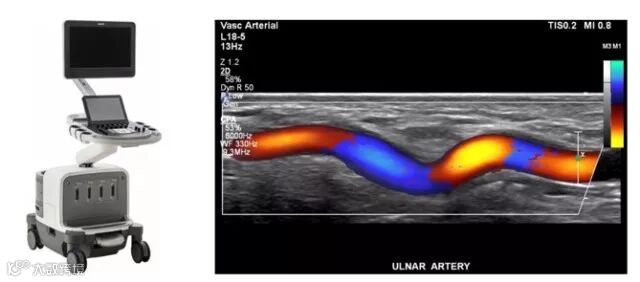

相比于X射线和CT,超声波对人体没有损伤,因此常用于产检。超声成像虽然图像看起来渣渣,但是它时间分辨率高,也就是说,可以实时地拍视频,而不是半天才扫出几张照片。另一个厉害之处是,超声能够测出血流流速等功能参数,对于一些血管疾病的诊断意义重大。

超声扫描仪和典型的血管超声图像(颜色代表流速和流向)